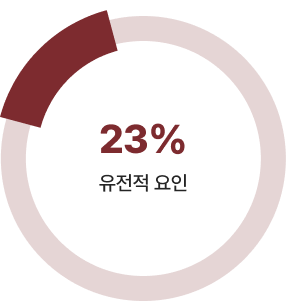

유전적 요인 VS 후천적 요인

키를 결정짓는 요인은 유전 23%, 후천 77%